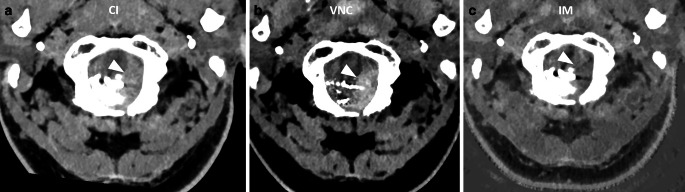

Methods: This retrospective study included 25 patients treated between April 2021 and March 2024, who underwent PCD-CT imaging post-embolization for intracranial arteriovenous malformations (AVM), dural arteriovenous fistulas (dAVF), spinal tumors, or middle meningeal artery (MMA) embolization for chronic subdural hematomas (cSDH). Imaging analysis involved iterative reconstruction, using conventional images (CI), iodine maps (IM), and virtual non-contrast (VNC) series. Two blinded neuroradiologists assessed the suppression quality of the embolic agents on a Likert scale.

Results: Of the 25 patients, 22 underwent intracranial and 3 spinal embolizations. The differentiation between iodine and tantalum-based embolics achieved 92% accuracy for reader 1 and 88% for reader 2, with a Cohen's kappa coefficient of 0.92 indicating high inter-reader agreement. Iodine-based agents were moderately suppressed, whereas tantalum-based agents exhibited superior suppression. Errors arose from mistaking suppressed platinum coils for tantalum-based embolics. Hemorrhage detection accuracy was high, with a Cohen's kappa of 0.92.